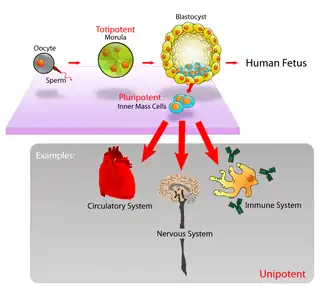

Embryonic stem cells (ESCs) are pluripotent stem cells derived from the inner cell mass of a blastocyst, an early-stage pre-implantation embryo.[1][2] Human embryos reach the blastocyst stage 4–5 days post fertilization, at which time they consist of 50–150 cells. Isolating the inner cell mass (embryoblast) using immunosurgery results in destruction of the blastocyst, a process which raises ethical issues, including whether or not embryos at the pre-implantation stage have the same moral considerations as embryos in the post-implantation stage of development.[3][4]

Embryonic stem cells (ESCs), derived from the blastocyst stage of early mammalian embryos, are distinguished by their ability to differentiate into any embryonic cell type and by their ability to self-renew. It is these traits that makes them valuable in the scientific and medical fields. ESCs have a normal karyotype, maintain high telomerase activity, and exhibit remarkable long-term proliferative potential.[6]

Embryonic stem cells of the inner cell mass are pluripotent, meaning they are able to differentiate to generate primitive ectoderm, which ultimately differentiates during gastrulation into all derivatives of the three primary germ layers: ectoderm, endoderm, and mesoderm. These germ layers generate each of the more than 220 cell types in the adult human body. When provided with the appropriate signals, ESCs initially form precursor cells that in subsequently differentiate into the desired cell types. Pluripotency distinguishes embryonic stem cells from adult stem cells, which are multipotent and can only produce a limited number of cell types.